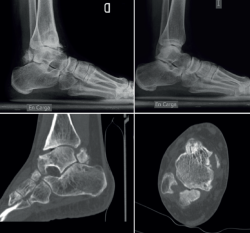

Figura 6. Enfermedad de Trevor. Displasia epifisaria hemimélica en un adulto. Radiografías en carga de ambos pies, cortes axiales y reconstrucción sagital de tomografía computarizada que muestran afectación del pie derecho con un fragmento óseo irregular y cambios degenerativos en la articulación tibioastragalina con deformidad del astrágalo. Pie izquierdo sano.